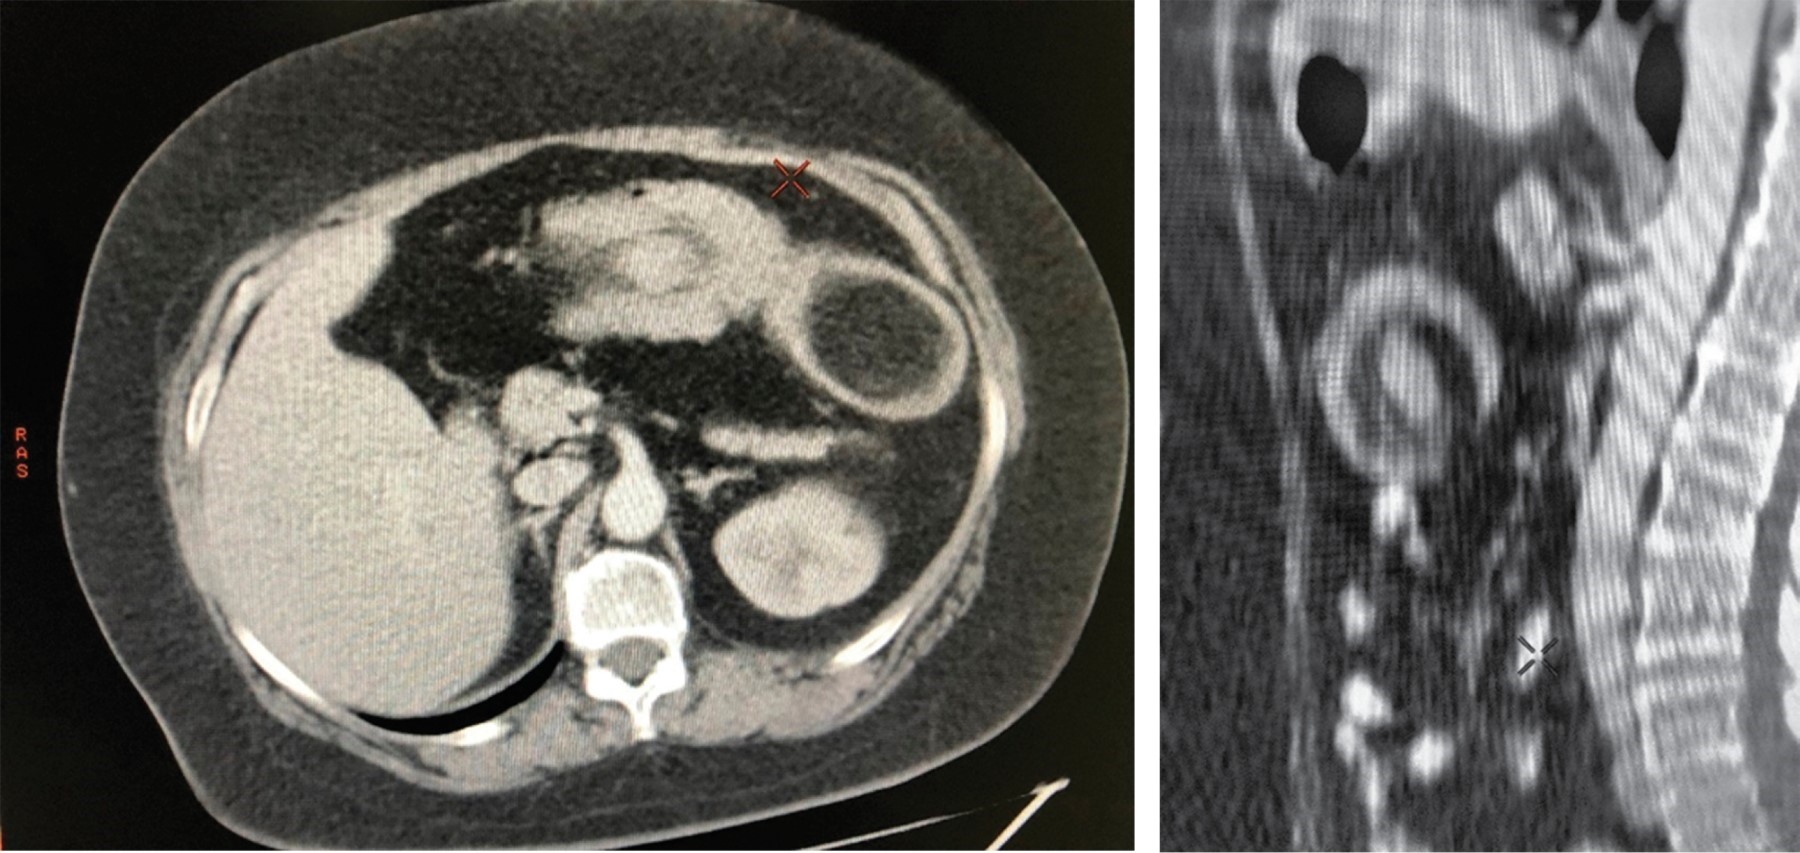

Contrast tomography (CT) scan of the abdomen showed, at the level of the transverse colon, a well-demarcated tumor, measuring 4.6 × 7.7 × 6.5 cm, with a density of 115 Hounsfield units (a quantitative scale used in CT scans to describe the different levels of tissue radiodensity), invaginated into the lumen of the transverse colon itself and with a discrete inflammatory process of the perilesional fat (Figure 1).

Abdominal CT scan (with oral and intravenous [IV] contrast) is the most sensitive (71 to 87%) and specific (close to 100%) imaging method because the mass with fat density (80-120 Hounsfield units) and the classic target sign or sausage-shaped mass is seen.10,11 Ultrasound can also provide data to guide the diagnosis; however, as it is an operator-dependent imaging study its sensitivity and specificity vary.12

Figure 1